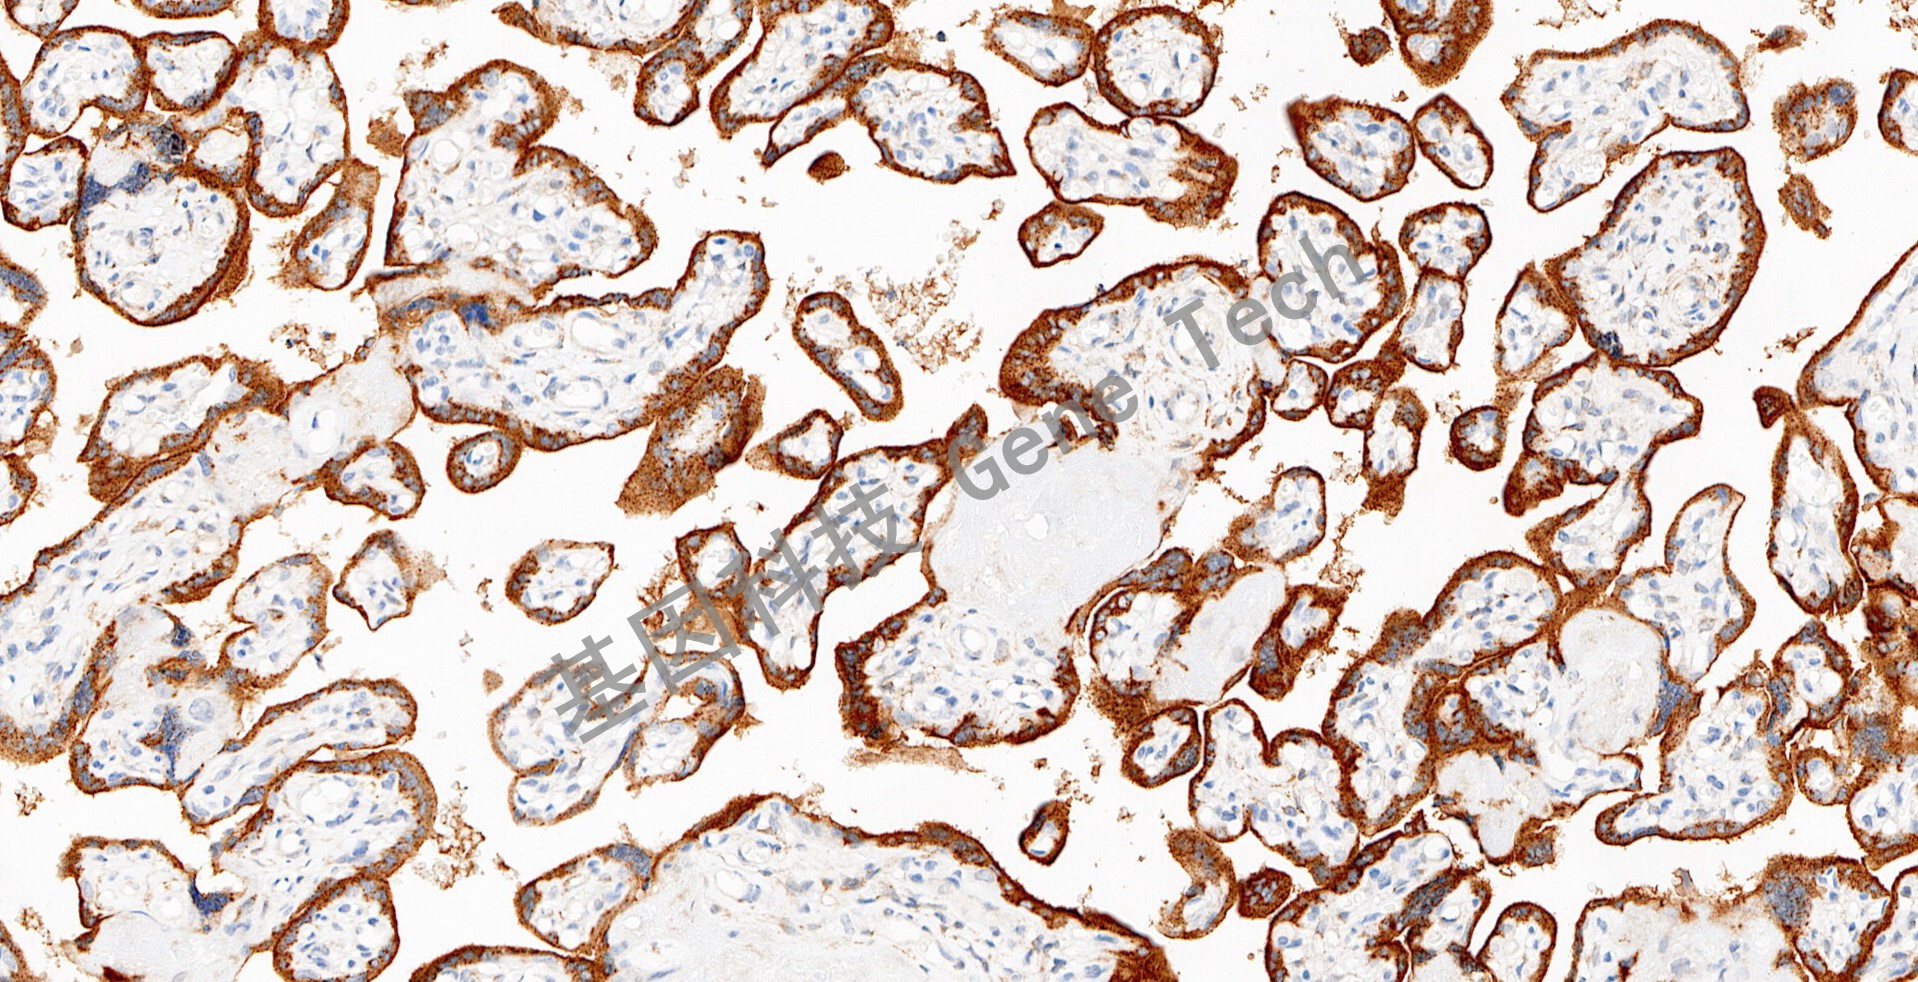

胎盘石蜡切片,用 Glypican-3(GT2068)染色,细胞膜/细胞浆阳性,DAB 显色。